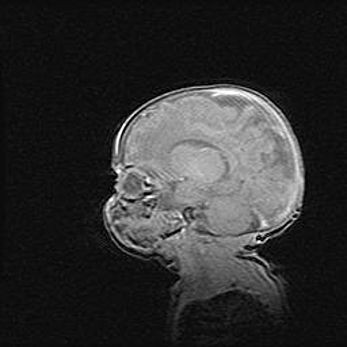

Неполная лизэнцефалия (пахигирия). Открытая гидроцефалия.

Возраст: 17 дней

Вес: 3110 г

Пол: мужской

Окружность головы: 33,5 см

Срок гестации: 35-36 недель

Лизэнцефалия—недоразвитие корковой пластинки и мозговых извилин в результате нарушения миграции нейронов коры. Поверхность мозговых полушарий гладкая. Микроскопически выявляется отсутствие нормальных слоев коры и скопление групп нейронов в подкорковом белом веществе.

Пахигирия—уменьшение числа вторичных извилин. В пораженном полушарии нервные клетки образуют толстый недифференцированный слой с неправильно расположенными нервными волокнами и группами гетеротопных клеток. Нервные клетки незрелые. Белое вещество истончено. При этом нередко аномально развит корково-спинномозговой путь.